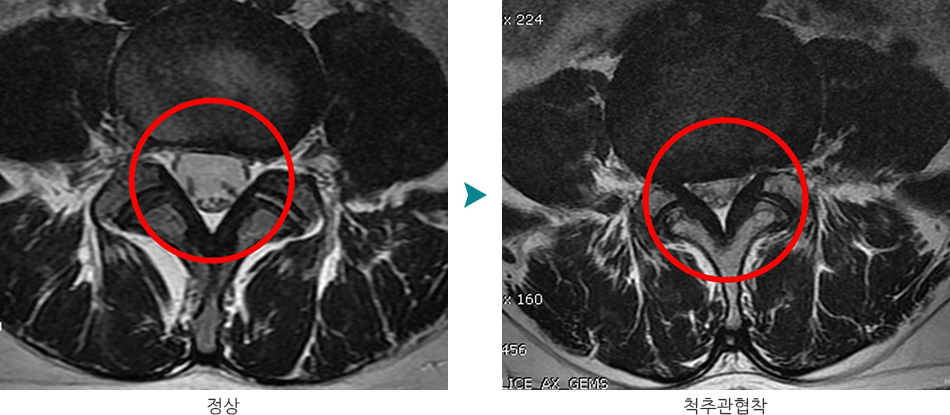

척추 협착증은 척추 내의 신경통로가 좁아지는 상태를 의미하며, 이는 신경이 압박받아 다양한 증상을 유발하게 됩니다. 주로 노화에 따라 발생하지만, 외상, 유전적 요인, 혹은 특정 질환이 원인이 될 수 있습니다. 척추 협착증의 주요 원인으로는 다음과 같은 사항들이 있습니다.

- 영상 검사: X선, MRI, CT와 같은 검사로 척추의 구조적 문제를 확인합니다. 이를 통해 신경이 얼마나 압박받고 있는지에 대한 정보를 제공합니다.